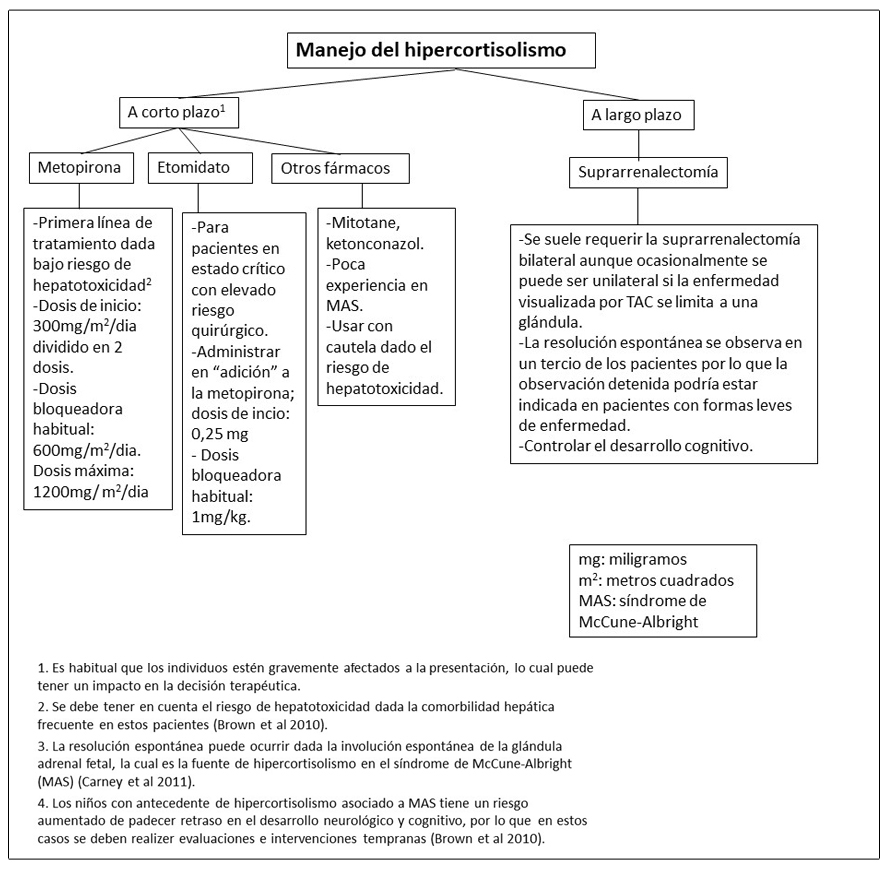

- Ver Figura 16; es difícil establecer guías de práctica clínica especificas dada la rareza del síndrome de Cushing neonatal.

- Se prefiere sobre el ketoconazol en niños con alteraciones hepáticas.

- La decisión de realizar o retrasar la adrenalectomía se debe individualizar, teniendo en cuenta la severidad de la enfermedad, la capacidad de controlar los niveles de cortisol con el tratamiento farmacológico, y los efectos potenciales del hipercortisolismo continuo sobre el desarrollo neuronal.

Figura 16. Recomendaciones para el manejo del exceso del hipercortisolismo en pacientes con Displasia Fibrosa/Síndrome de McCune-Albright